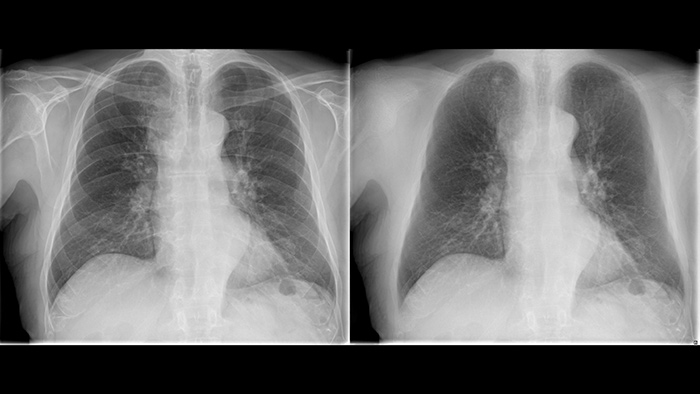

Philips UNIQUE 2 improves image quality with more homogeneous black backgrounds, reduced noise and automatic enhancement of small details

Philips Bone Suppression3 helps remove bone structures from chest images for an unobstructed view of soft tissue and can improve actionable nodule detection by up to 16.8% without the need to expose the patient to additional X-ray dose.4